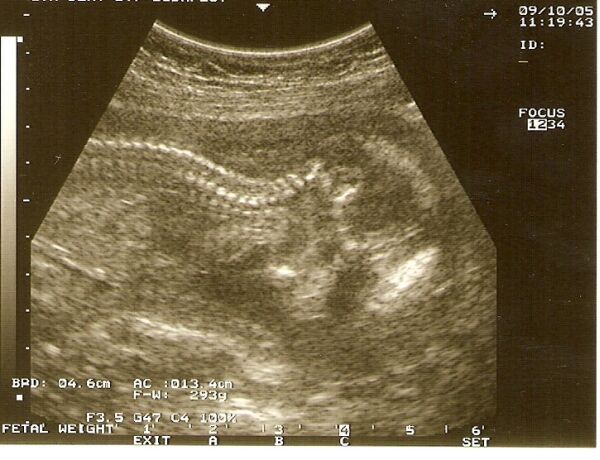

Beszkenneltem Berci legutóbbi fotóját - lefelé néz, és már olyan nagy, hogy csak derékig fér a képre! :)

Kép

boruska: Berci baba tényleg szép nagy már.

Boruska! Szép nagy már a legénykéd, szépen látszik a gerince!